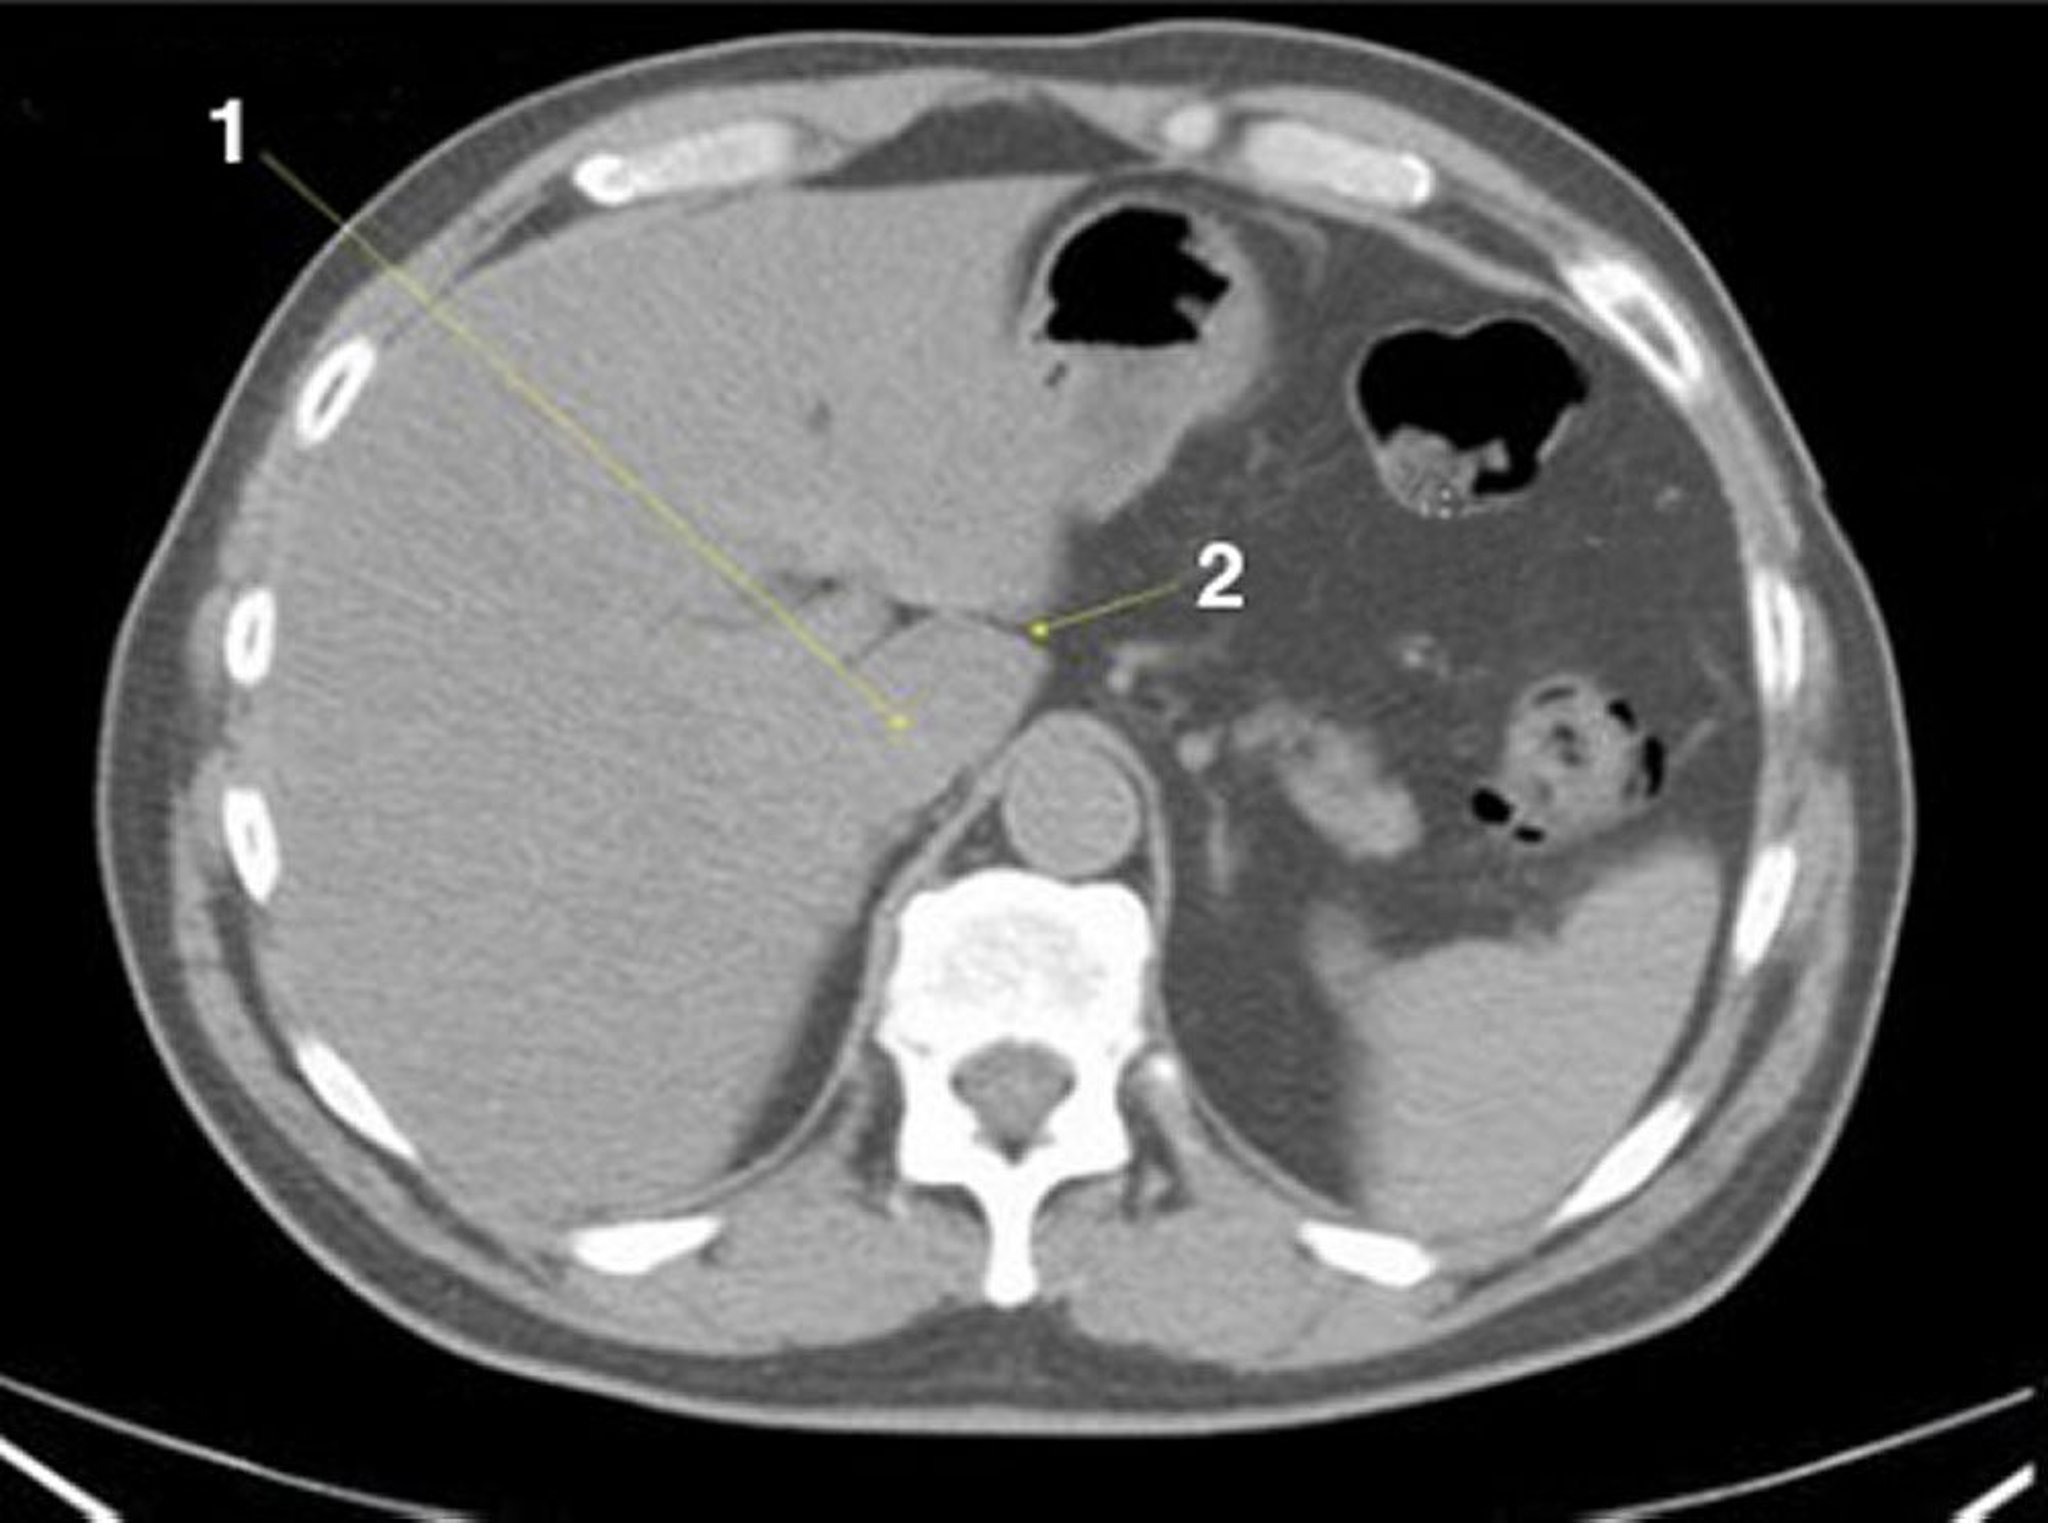

Tomografía computarizada sin contraste de abdomen y pelvis que muestra anatomía normal (corte 4)

1 = lóbulo caudado del hígado; 2 = fisura del ligamento venoso.